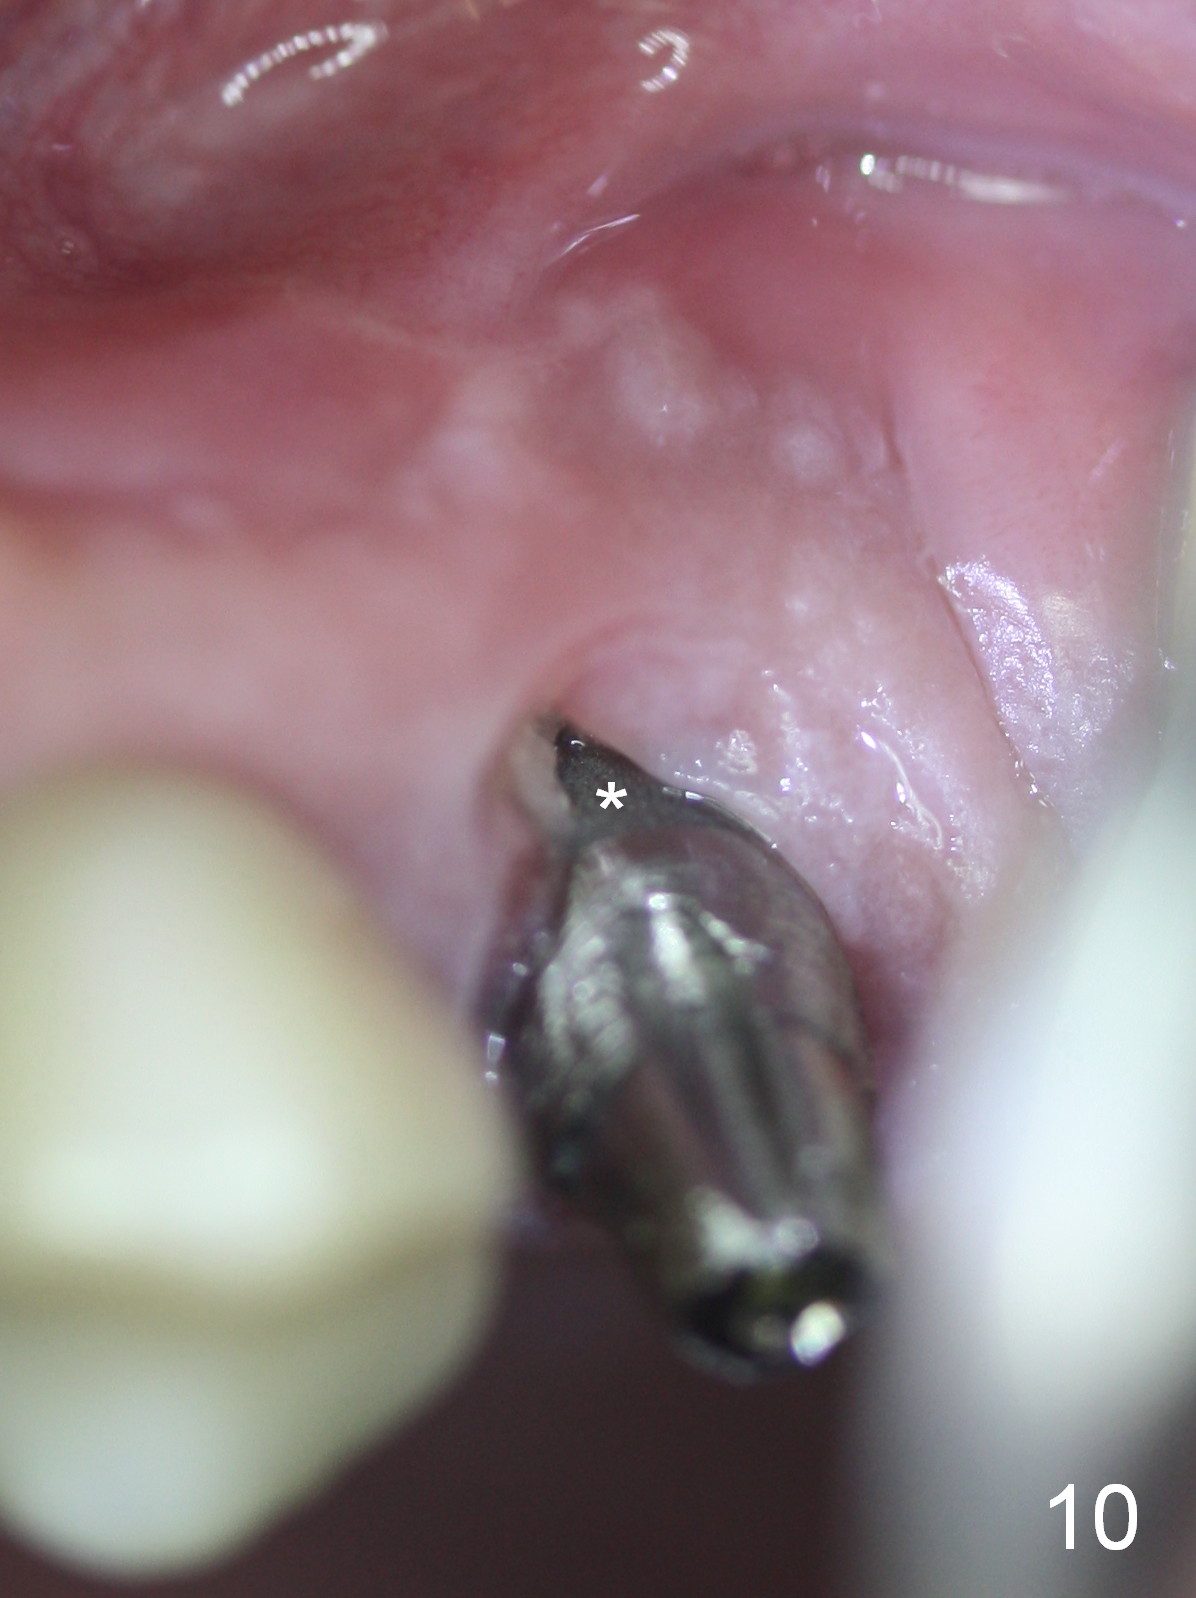

The patient returns 7 days postop, reporting that the provisional has been dislodged several times. The gingiva adapts to the provisional with occlusal clearance (Fig 8 *). The rough surface of the implant is exposed (Fig.9,10 *). It appears that some of bone graft has been lost. The provisional should be trimmed so that the gingiva may be able to grow over the rough surface.